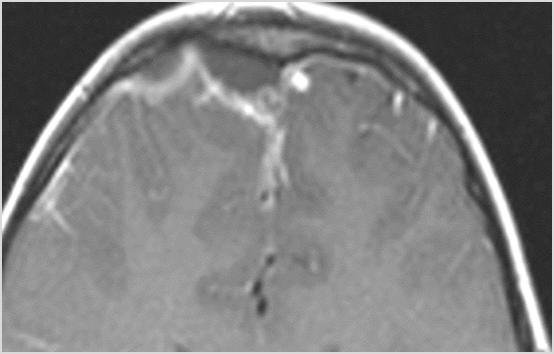

Intracranial

There is a subperiosteal fluid collection or abscess along the boney walls of the anterior or middle cranial fossa. [Yes/No]

There is an epidural fluid collection or abscess along the boney walls of the anterior or middle cranial fossa. [Yes/No]

There is a subdural fluid collection or abscess along the boney walls of the anterior or middle cranial fossa. [Yes/No]

There is a subdural fluid collection or abscess along the falx cerebri or within the tentorium. [Yes/No]

There is evidence of thrombus, thrombophlebitis or other occlusive or inflammatory process of the cortical veins, sphenoparietal sinus or sagittal sinus. [Yes/No]

There is evidence of thrombus, thrombophlebitis or other occlusive or inflammatory process of the cavernous sinus. [Yes/No]

There is evidence of inflammation of the distal internal carotid artery. [Yes/No]

There is evidence of an infectious aneurysm. [Yes/No]

There is brain edema specifically involving the frontal and temporal lobes. [Yes/No]

There is cerebritis specifically involving the frontal and temporal lobes. [Yes/No]

There is brain abscess specifically involving the frontal and temporal lobes. [Yes/No]

There is likely meningitis, meningoencephalitis with complicating hydrocephalus or brain herniation. [Yes/No]